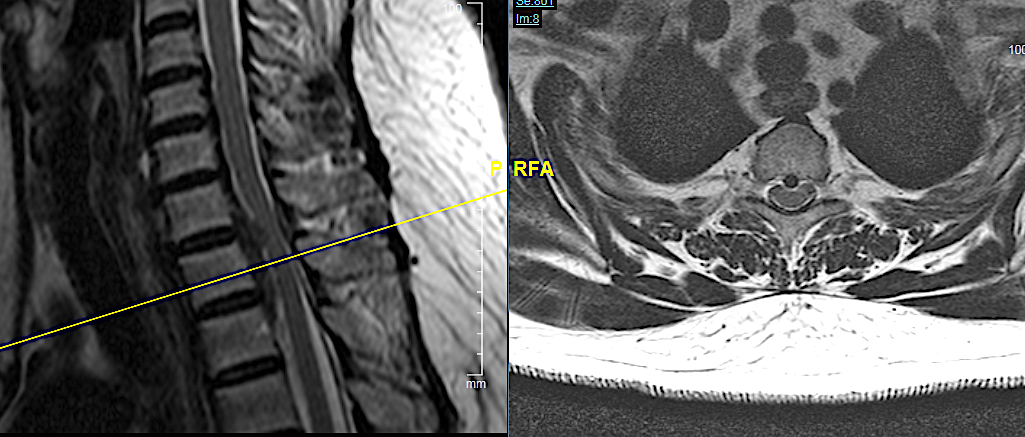

CASO CLÍNICO 2: HERNIA DISCAL C7-TH1 ASOCIADA A ESTENOSIS DE CANAL

Paciente de 46 años que consulta por clínica de mielopatía cervical de evolución progresiva en los últimos dos meses. Tuvo una braquialgia derecha 4 meses antes que mejoró con tratamiento conservador.

Este caso me parece interesante porque hubiese podido ser tratado por vía posterior al ser una hernia lateral, sin embargo, no se trataba de una afectación segmentaria aislada sino que en la misma RM podía apreciarse estenosis de canal en C6-C7 con compresión medular a dicho nivel. No hay que olvidar que el motivo de la consulta fue la instauración de una mielopatía cervical progresiva (inestabilidad, urgencia miccional e hiperreflexia) pues la braquialgia derecha estaba en proceso de remisión.

Por las razones expuestas, a pesar de un thoracic inlet angle bastante alto, opté por realizar un abordaje anterior con descompresión + artrodesis IS con cajas atornilladas C7-Th1.